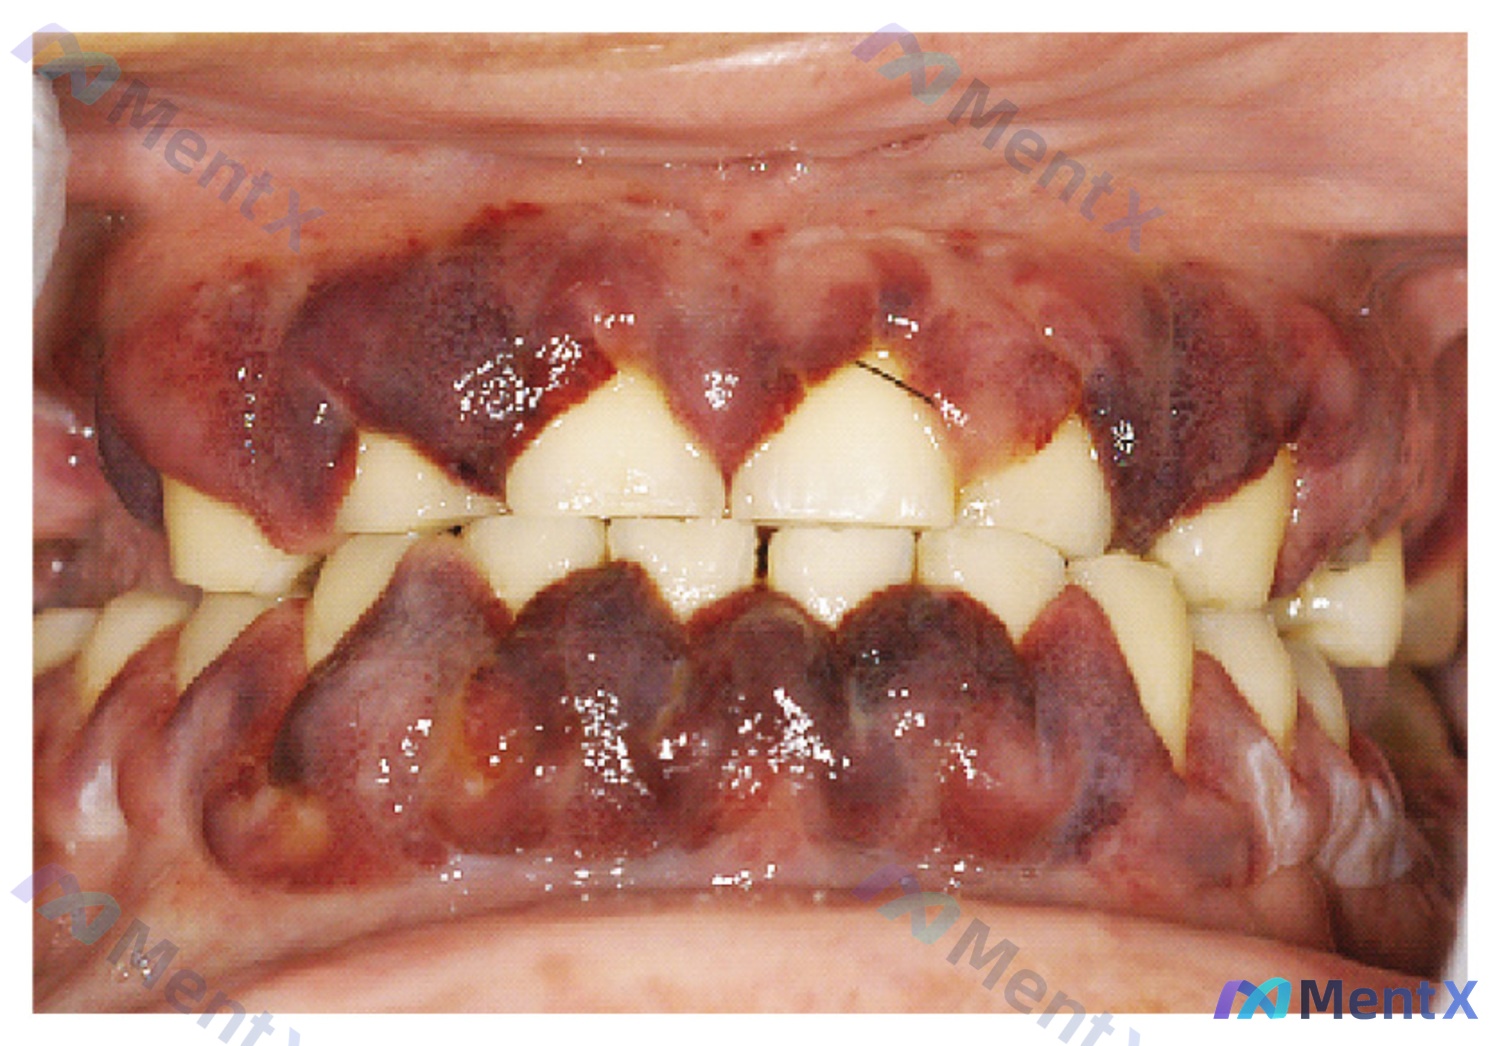

整理了一个资料比较完整的病例,觉得分析路径挺有代表性,和大家分享一下。 病例核心信息 - 主诉/全身表现:疲劳、发热、厌食、体重意外减轻 - 口腔影像关键特征(来自图像分析): 1. 颜色:全口牙龈弥漫性深紫色、暗红色、紫黑色,非散在出血 2. 形态:龈乳头肿胀圆钝呈球状,失去刀刃状边缘,明显覆盖部...